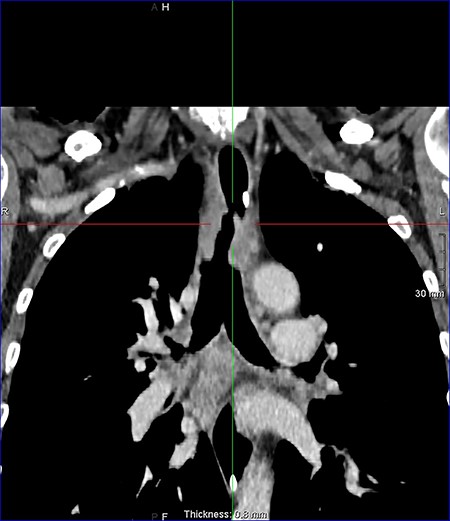

On examination, the patient had no obvious abnormality in the valve puncture. The stoma site was normal except for some crusting around the edges. A marked abnormality on the tracheal wall ~6 cm inferior to the stoma site was revealed, through a flexible nasal endoscopic examination. The abnormality was later confirmed to be a TOF. The patient underwent a computed tomography (CT) scan to delineate the surrounding anatomy as to facilitate the planning of the surgery (Figs 2–4).

Axial reconstruction post contrast CT neck and thorax images with 4 mm defect/tracheoesophageal fistula located 8–9 cm from tracheostomy level and 12 cm proximal to the carina.